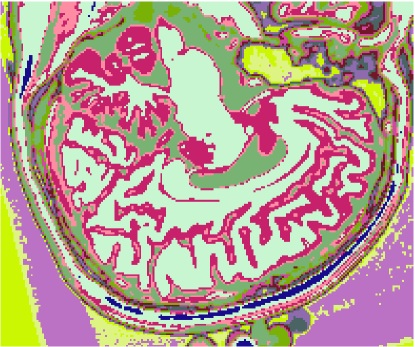

A figura 6 mostra os resultados de classificação, enquanto a figura 7 exibe os resultados de quantização para a imagem sem ruído da fatia 97, figura 5, usando os métodos KO, CM, KM, ODC-PME e ODC-CAN. Esses resultados ilustram qualitativamente as diferenças entre os métodos de classificação e quantização, dado que a fatia 97 possui todas as 13 classes presentes na análise [51].

Figura 6: Composição colorida R0-G1-B2 das imagens da fatia 97 ponderadas em PD, T1subscript𝑇1T_{1} e T2subscript𝑇2T_{2} (a) e resultados de classificação usando os métodos KO (b), CM (c), KM (d), ODC-PME (e) e ODC-CAN (f)

A tabela 2 mostra os resultados da avaliação dos métodos de classificação não supervisionada quanto à quantização vetorial, usando os índices de fidelidade ϵMEsubscriptitalic-ϵME\epsilon_{\textnormal{ME}}, ϵMAEsubscriptitalic-ϵMAE\epsilon_{\textnormal{MAE}}, ϵMSEsubscriptitalic-ϵMSE\epsilon_{\textnormal{MSE}}, ϵRMSEsubscriptitalic-ϵRMSE\epsilon_{\textnormal{RMSE}} e ϵPSNRsubscriptitalic-ϵPSNR\epsilon_{\textnormal{PSNR}}, considerando todas as 181 fatias com 3 bandas (DP, T1subscript𝑇1T_{1} and T2subscript𝑇2T_{2}), para os métodos KO, CM, KM, ODC-PME e ODC-CAN e 0% de ruído. Já os gráficos das figuras 8, 9, 10 e 11 mostram os resultados em função do nível percentual de ruído para os diversos métodos, para um total de 6 volumes de 181 fatias de 3 bandas, totalizando 1086 imagens coloridas, ou 3258 imagens em níveis de cinza.

Figura 7: Composição colorida R0-G1-B2 das imagens da fatia 97 ponderadas em PD, T1subscript𝑇1T_{1} e T2subscript𝑇2T_{2} (a) e resultados de quantização usando os métodos KO (b), CM (c), KM (d), ODC-PME (e) e ODC-CAN (f)